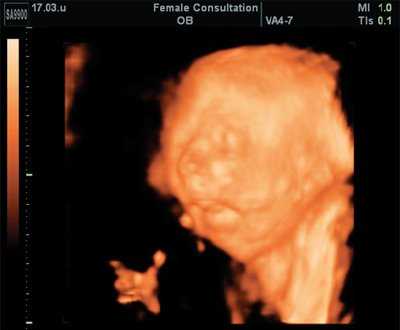

Немаловажное значение для оценки лицевых структур плода и четкой идентификации выявленных изменений имело дополнительное использование трехмерной эхографии [3]. Специфические изменения лица плода были заметны "с первого взгляда". При анализе объемных реконструкций была четко видна гипоплазированная нижняя челюсть и близко расположенные глазные яблоки (гипотелоризм) (рис. 7, 8). Аномалий развития других органов не выявлено.

Рис. 7. Гипотелоризм плода в 22 недель беременности (поверхностная реконструкция).

Рис. 8. Микрогения плода в 22 недель беременности (поверхностная реконструкция).